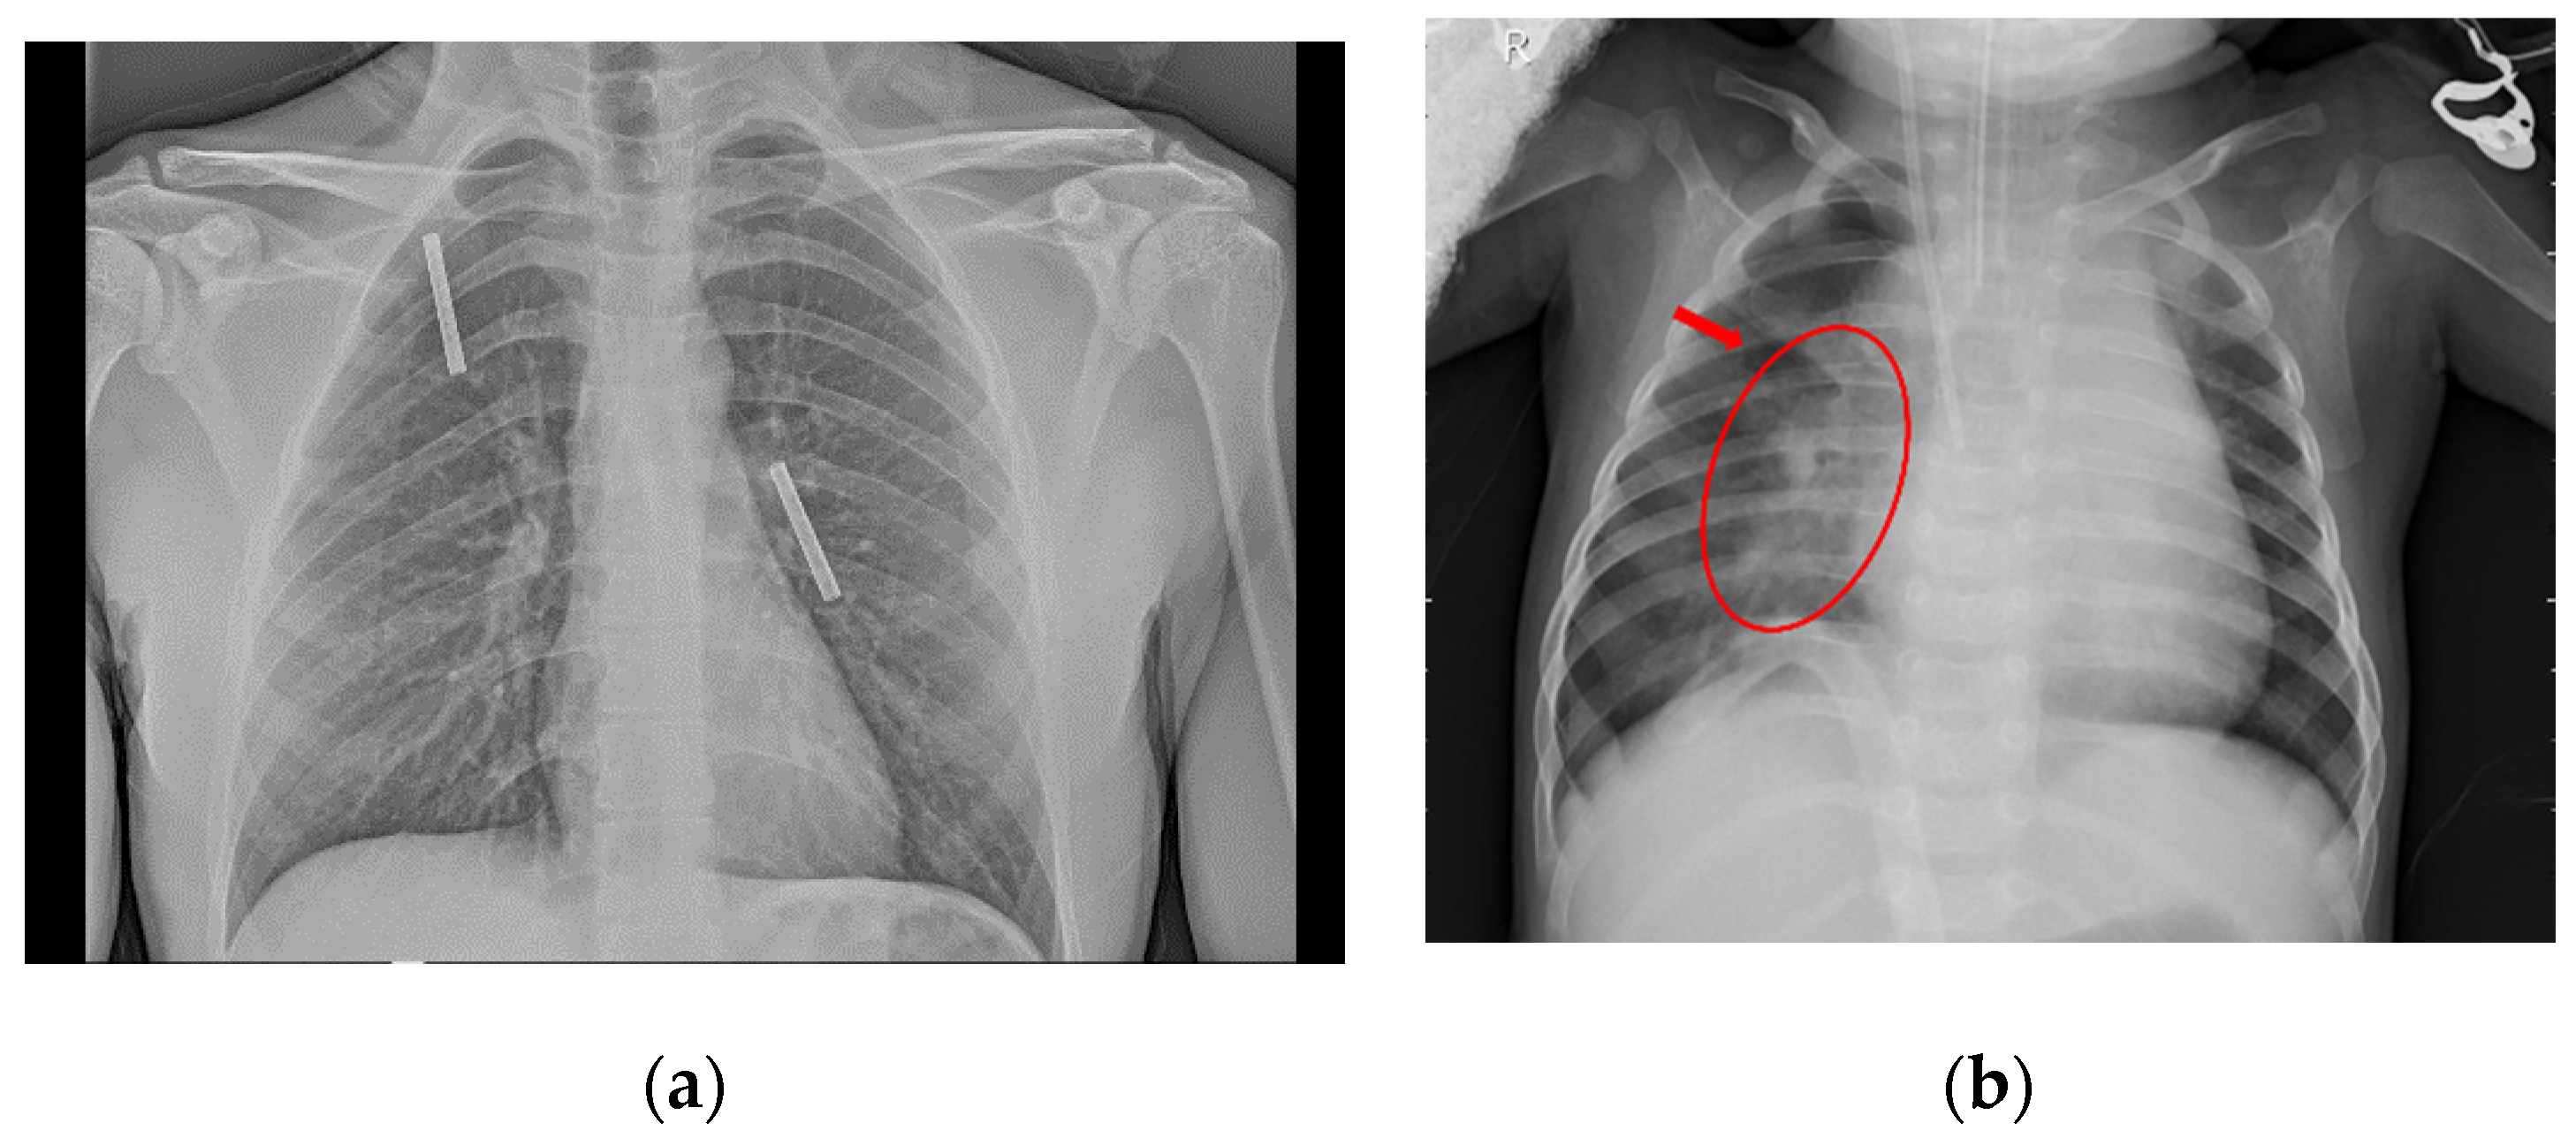

3.4. Convolutional Network

4. Proposed Method

4.1. Image Preprocessing

- If some black band appears at the edges, they are removed.

- The size of the image is transformed until the smallest border measures 299 pixels.

- Extract the central region of 299 × 299 pixels.